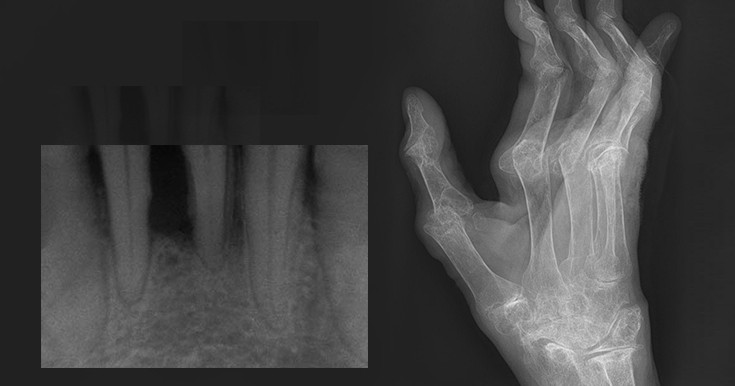

Диагностика ревматоидного артрита